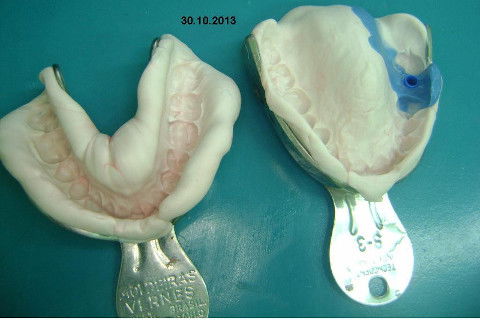

Instalação de um implante em região do 26. Utilizamos um implante cone morse Alvim Neodent 4.3 X 11,5. Foi uma cirurgia muito rápída e minimamente traumática, sem retalho e sutura.

Fotos do caso